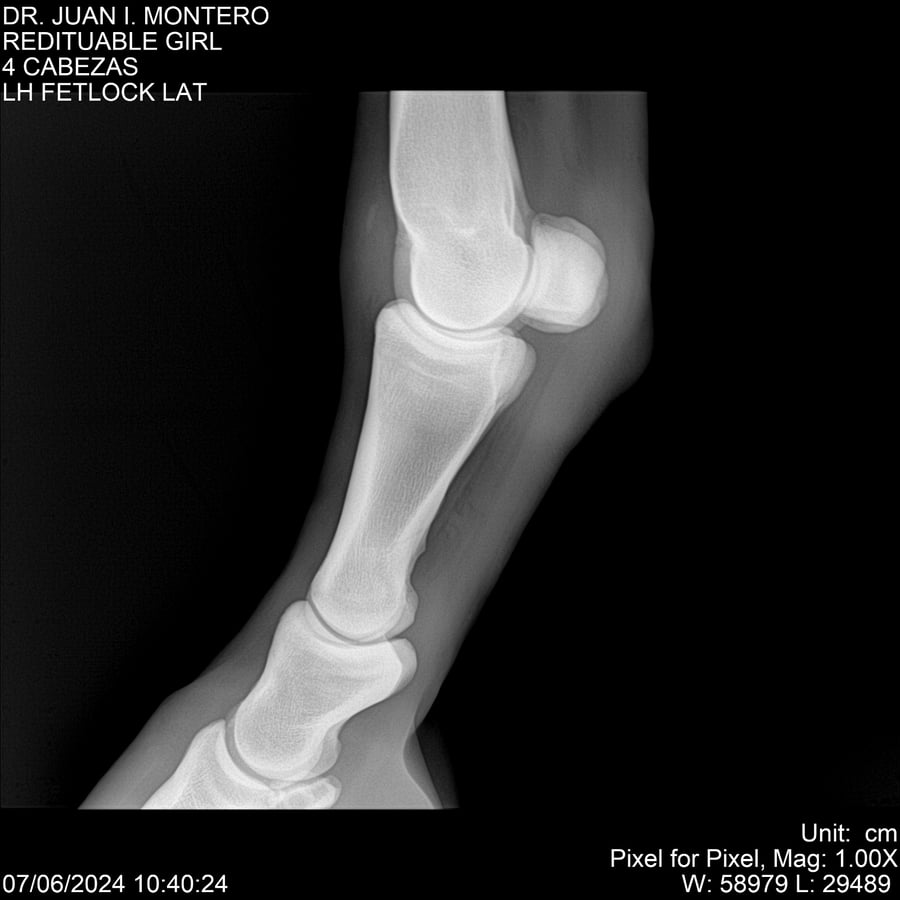

LOTE 19, REDITUABLE GIRL Lote Anterior Volver al remate Lote Siguiente Ficha Contacto Montevideo - Ficha del Lote Identificador: #281096 Categoría: Yeguarizos Montevideo - 79 Visualizaciones ClicData Contacto Empresa: Abelenda N. R., Walter Hugo Nombre*: Teléfono* : E-mail* : Mensaje Enviar Registrese gratis Este contenido Exclusivo está disponible sólo para usuarios registrados Ingresar